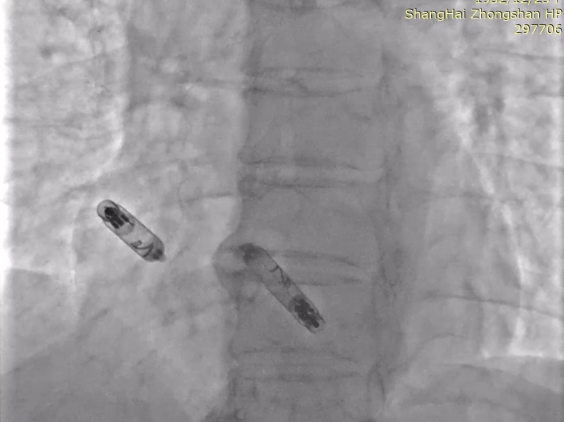

以上两位患者均以标准流程成功植入Aveir™ DR,最终固定位置影像:

病例1 RAO

病例1 LAO

病例2 RAO